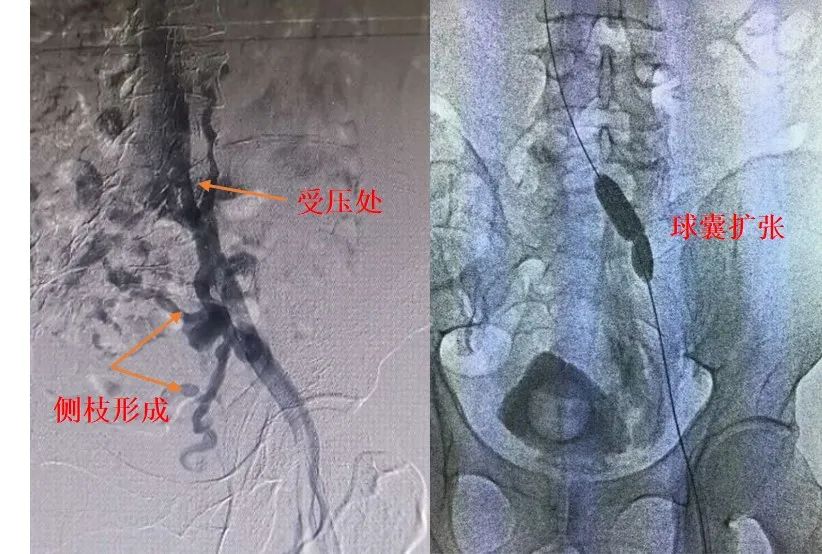

数字减影血管造影:静脉插管造影仍为髂静脉综合征诊断的金标准,发现髂静脉狭窄和血栓后应积极经皮穿刺插管,经导管直接溶栓或取栓。造影可直接显示左髂总静脉受压段横径增宽,不同程度的充盈缺损影,受压段静脉的前后壁粘连或束带形成,还可间接显示盆腔内侧支循环、腰升静脉侧支循环形成。

对于伴有下肢静脉慢性高压或静脉功能不全症状严重者,髂总静脉狭窄程度>50%,静息时狭窄两端压力差>2毫米汞柱(1毫米汞柱=133.322帕)或活动时>3毫米汞柱,腔内超声发现髂静脉内存在>50%的狭窄或隔膜,或狭窄远端大量侧支血管开放者均应首选介入治疗。导管接触溶栓、球囊扩张和支架植入术可酌情选择使用。

髂静脉扩张成形,髂静脉主干阻塞无论是严重狭窄或是完全闭塞,都需要解除阻塞以恢复下肢静脉回流;膜性阻塞与短节段狭窄可先单纯球囊扩张成形治疗。